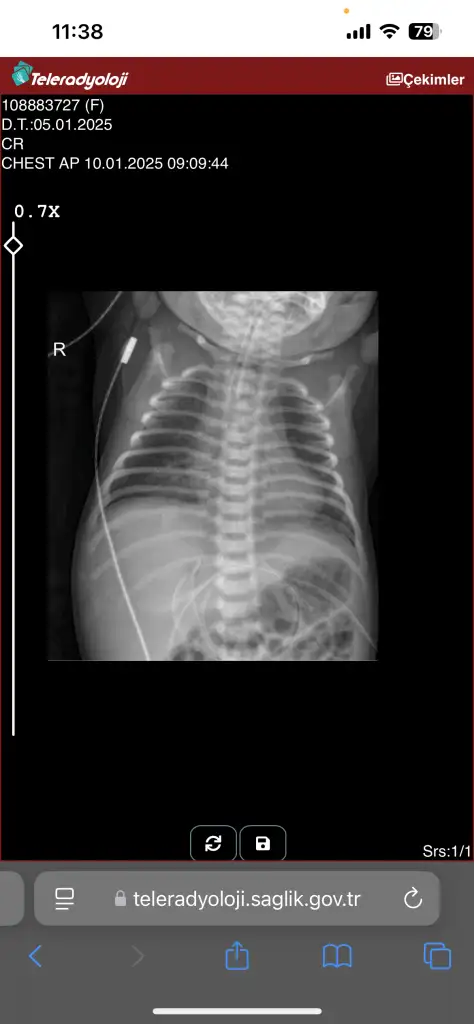

Ayın 10 unda çekilen röntgne bu. Cumartesi pazar çekilmiyormuş. Size çok çok teşekkür ederim bu arada

Sol tarafta beyazlıklar var ya onun bir kısmı kalbin gölgesi ama yine de yukarı doğru biraz beyazlık var yani oralara oksijen gitmemiş. Şimdi entübe edildiği için basınçla oraya oksijen verecekler ciğerleri toparlanacak. İlaç tedavisi ile de iltihap gerilecek inşallah. Biraz zayıf mı doğdu haftasıyla uyumlu muydu evladınız ?

Doktor durumunda ya da bağlı olduğu monitörde kötüle gidiş görürse yeniden çekerler. Stabil ise bebeği maruz bırakmamaya çalışıyorlar. Yoğun bakımlarda mantık böyle bebek iyiyse minimum temas minimum işlem. Biz istiyoruz anne olarak hep baksınlar hep kontrol etsinler ama yoğun bakımların sistemi böyle değil. Sabırlı olacağız başka bir çaremiz yok :)